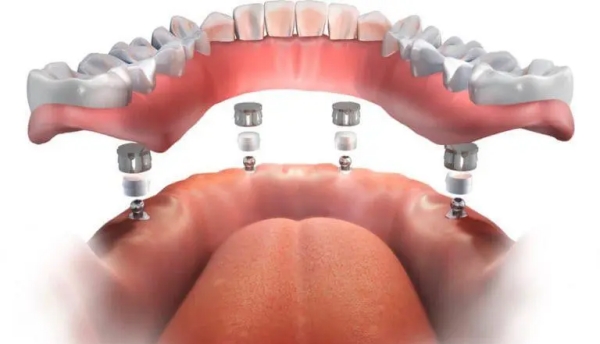

根據(jù)CBCT和口內(nèi)掃描的數(shù)據(jù),醫(yī)生在專門種植軟件上完成種植方案設(shè)計(jì)后,會(huì)通過3D打印技術(shù)制作個(gè)性化手術(shù)導(dǎo)板。這個(gè)導(dǎo)板能穩(wěn)準(zhǔn)地將術(shù)前設(shè)計(jì)轉(zhuǎn)移到手術(shù)中,確保種植體植入在預(yù)定位置。

設(shè)計(jì)方案確認(rèn)后,通過3D打印技術(shù)制作個(gè)性化手術(shù)導(dǎo)板。導(dǎo)板的精度直接影響種植的恰當(dāng)性,中諾口腔在這方面有嚴(yán)格的質(zhì)量把控。

手術(shù)當(dāng)天,醫(yī)生將導(dǎo)板固定在你的牙床上,然后沿著導(dǎo)板預(yù)留的孔位逐級(jí)備孔、植入種植體。整個(gè)過程穩(wěn)準(zhǔn)有效,不需要臨時(shí)判斷。